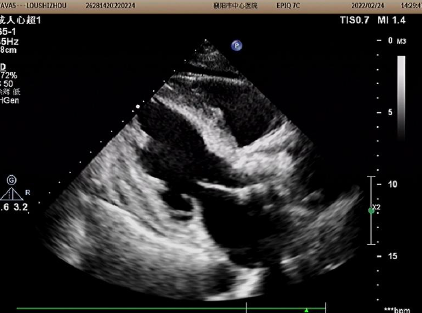

2022年1月25日超声图像

主动脉瓣峰值流速:4.14M/S;平均跨瓣压差:69mmHg;左室射血分数EF值:29%。